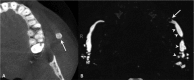

Inflammatory and obstructive disorders of the salivary glands are caused by very different pathological conditions affecting the gland tissue and/or the excretory system. The clinical setting is essential to address the appropriate diagnostic imaging work-up. According to history and physical examination, four main clinical scenarios can be recognised: (1) acute generalised swelling of major salivary glands; (2) acute swelling of a single major salivary gland; (3) chronic generalised swelling of major salivary glands, associated or not with "dry mouth"; (4) chronic or prolonged swelling of a single major salivary gland. The algorithm for imaging salivary glands depends on the scenario with which the patient presents to the clinician. Imaging is essential to confirm clinical diagnosis, define the extent of the disease and identify complications. Imaging techniques include ultrasound (US), computed tomography (CT) and magnetic resonance (MR) with MR sialography.